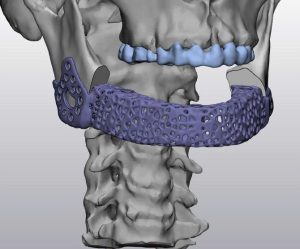

Hình ảnh trên minh họa quá trình thiết kế mô hình implant xương hàm dưới dựa trên dữ liệu CT-Scan. Các bác sĩ và kỹ sư sử dụng phần mềm chuyên dụng để:

Tái tạo cấu trúc xương 3D từ dữ liệu hình ảnh y khoa.

Thiết kế implant cá thể hóa: implant được tối ưu về hình dạng, độ dày, và lỗ thoát nhằm tăng cường sự tích hợp sinh học và lưu thông máu.

Mô phỏng phẫu thuật: cho phép bác sĩ xem trước kết quả phẫu thuật, giảm rủi ro và thời gian mổ.

Nhờ công nghệ in 3D, các mô hình implant được chế tạo với độ chính xác đến từng milimet, hỗ trợ phục hồi chức năng nhai và thẩm mỹ cho bệnh nhân sau phẫu thuật tái tạo xương hàm.